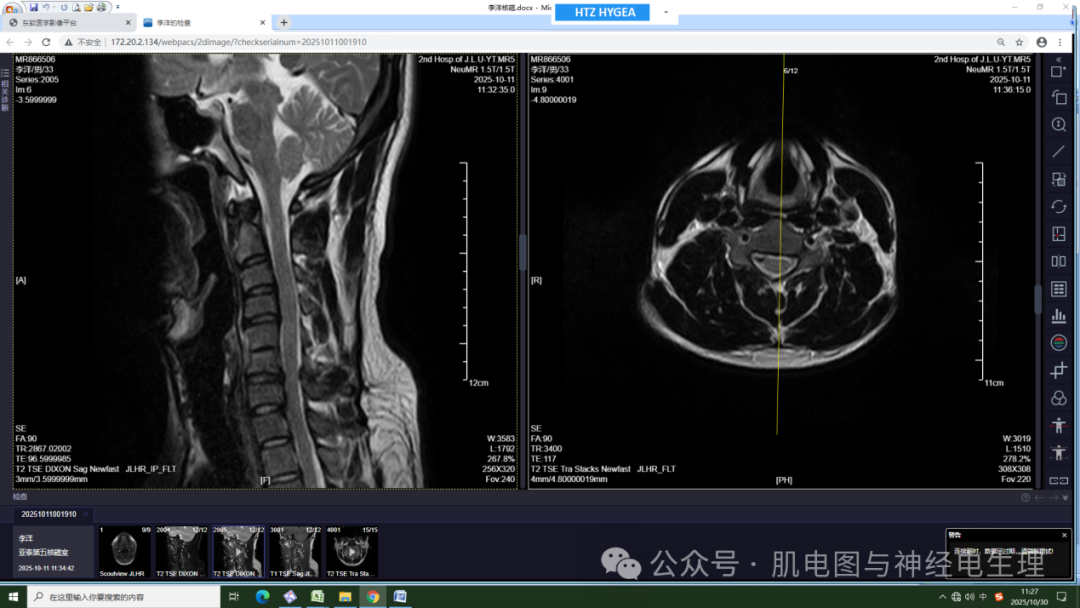

外院腰椎核磁:腰椎曲度存在,各椎体边缘变尖。胸11、腰5椎体边缘局限性凹陷,腰4、5椎体邻近缘见条片状稍长T1稍短T2信号,压脂像呈稍高信号。腰4-5、腰5骶1椎间隙变窄。腰4-5、腰5、骶1间盘信号减低,并向后方突出,以腰5骶1间盘向左后方突出为著。椎管及脊髓内未见异常信号。